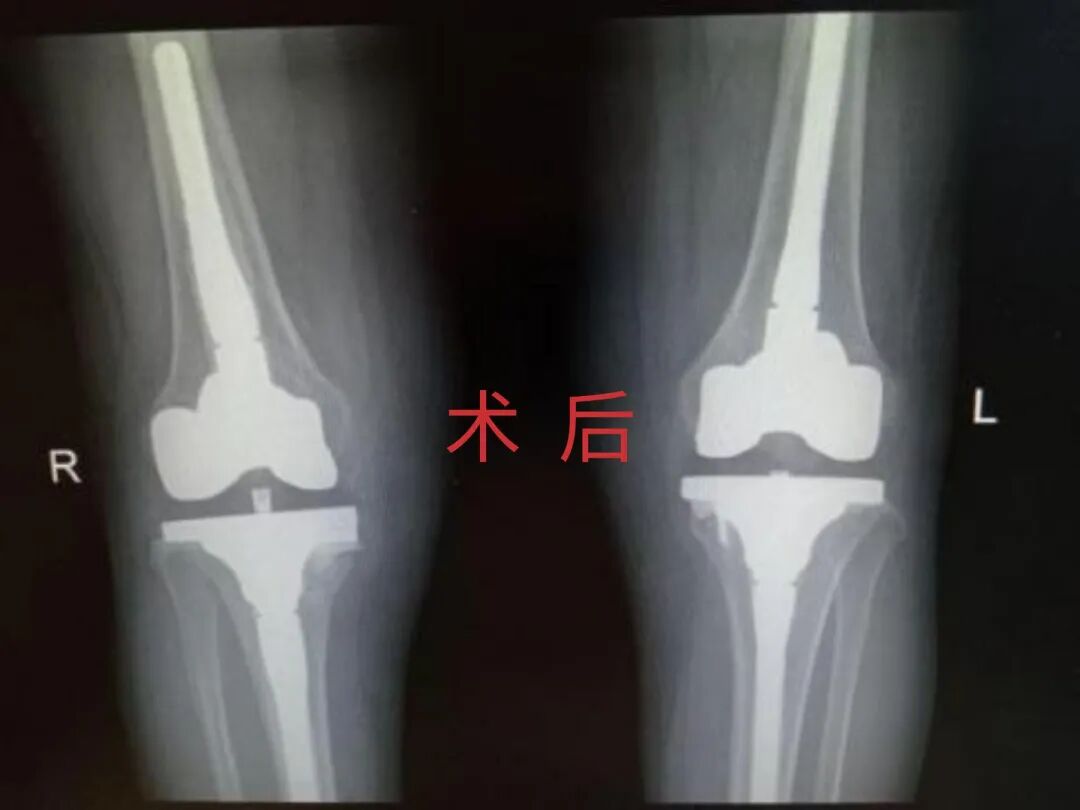

12月17日,贵州航天医院第88次晨读会由我院骨一科主任、副主任医师陈明勇作学术交流,他以“肱骨近端骨折并肩关节脱位的手术治疗”为题,全面讲解了该损伤的手术策略、术中血供保护理念及内侧支撑重建技术等内容,并通过多个典型病例图文资料分享了从损伤机制分析、手术步骤实施到术后随访评估的完整过程与关键细节,为临床处理此类复杂骨折提供了较为全面的技术参考,有助于在手术规划中结合个体情况开展针对性治疗。 贵州航天医院 骨科专家简介 陈明勇 骨一科主任,副主任医师 临床擅长:从事创伤骨科工作约20年,对骨缺损、骨不连、骨肿瘤、肢体畸形等的肢体矫形重建及功能重建,慢性化脓性骨髓炎的根治治疗、糖尿病足的保肢治疗、快速康复理念(ERAS)下的老年骨折的诊治,四肢复杂骨折的诊治,四肢骨折等微创手术治疗具有丰富的临床经验。 2004年毕业于遵义医学院临床专业,曾在中国人民解放军总医院、广西医科大学第一附属医院、上海第六人民医院骨科进修。中国中西医结合学会骨伤科专业委员会横向骨搬移治疗糖尿病足及微血管网再生学组首届委员,遵义市医学会创伤分会常务委员。 瞿 晖 骨科党支部书记,骨二科主任,副主任医师 临床擅长:对骨科的常见病、关节外科、脊柱外科及运动医学疾病的诊治具有丰富的临床经验,熟练掌握骨科手术操作技术。 毕业于遵义医学院临床医学系,2005年前往广州中山大学第一附院骨显微医学部进修学习,2011年前往成都华西医院进修学习,并多次在省内外学习骨科相关知识,是中华医学会骨科分会会员。 赵小锋 中共党员,骨二科副主任,副主任医师 临床擅长:从事骨科临床工作11年,对骨科常见病、多发病诊疗有较为丰富的临床经验,擅长脊柱相关疾病诊断及治疗,尤其是颈、腰、腿疼痛疾病诊断及治疗,擅长胸腰椎骨折微创经皮穿刺内固定术、经皮穿刺椎体成形术、经皮穿刺脊柱内镜下腰椎间盘摘除术、单纯开创腰椎间盘摘除术、腰椎滑脱复位椎间植骨椎融合内固定术、腰椎管狭窄减压融合内固定术及人工髋、膝关节置换术等。 2012年毕业于遵义医学院外科学专业硕士研究生,2019年参加“遵义市115医学人才精英计划”于上海交通大学第一附属医院培训学习,2023年于北京大学第三人民医院脊柱外科进修学习,曾获得遵义市优秀医师荣誉称号。 遵义市手外科第一届委员,遵义市医学会创伤分会第一届委员,遵义市医学会创伤分会第二届委员,贵州省康复医学会第三届脊柱脊髓专业会委员,遵义市医学会烧伤与整形外科学分会委员,发表论文5篇,其中国家级核心期刊1篇,SCI论文1篇,主持市级课题1项并结题,参与市级课题2项。 赵兴东 骨科主任医师 临床擅长:擅长骨科的常见病及各种创伤、四肢骨折创伤修复、骨感染、手足疾病的诊治和手足体表畸形的矫形整复,熟练掌握骨科四肢骨病及创伤的手术操作技术,尤其在四肢关节复杂性损伤、手足外伤、组织缺损创面、难治创面的皮瓣修复方面及平足、高弓足矫形方面及四肢慢性疼痛诊治、康复方面具有丰富的临床经验。 硕士研究生,毕业于遵义医学院临床外科系,2015年前往山东省立医院手足外科进修学习;遵义市医学分会创伤分会第一、二届委员,遵义市手外科医学会第二委届员会常务委员;在省级及省级以上期刊发表文章9篇,参编著作2部,参与主持并完成市级课题1项,参与市级课题2项、省级课题1项。 张艳金 中共党员,骨科副主任医师 临床擅长:从事骨外科工作16年,对复合伤、多发伤的救治、四肢骨干骨折、关节周围骨折、骨肿瘤、骨髓炎等诊治具有丰富的临床经验。 中共党员,硕士研究生,2006年本科毕业于山西医科大学第二临床医学院,2011年研究生毕业于北京军区总医院;在“老年COPD患者合并髋部骨折的诊治”国际合作课题组研究两年,在老年髋部骨折的诊治方面具有丰富的经验,并发表论文6篇;主持遵义市级课题1项,承担遵义医科大学的临床教学工作,获得遵义医科大学优秀带教老师荣誉。编撰有《骨科疾病诊疗精粹》一书,开展2项新技术,编撰地方规范《务川自治县创伤骨科常见疾病诊疗规范》一书。 张俊凯 骨科副主任医师 临床擅长:从事骨科临床工作28年,对创伤骨折、骨感染、骨缺损、骨不连等外科诊治,四肢骨折的微创手术治疗,四肢复杂骨折(如关节内粉碎性骨折、多发骨折等)的损伤控制及手术治疗等具有丰富的临床经验。 1995年毕业于遵义医学院临床专业,2009年前往复旦大学附属医院骨科进修1年。 卢懿明 中共党员,骨科副主任医师 临床擅长:从事骨科工作18年,对创伤骨折、四肢骨折的微创手术治疗、四肢复杂骨折(如关节内粉碎性骨折、多发骨折等)的损伤控制及手术治疗,尤其是髋部骨折的PFNA等微创技术,踝关节骨折、膝关节周围骨折的Mipo微创技术等具有丰富的临床经验,开展了4项新技术,发明6项新型专利技术。 2005年毕业于遵义医学院临床专业,2017年,前往南方医科大学第三附属医院骨科进修半年,回院后运用Mipo技术对骨干骨折及干骺端骨折的治疗技术,同时积极开展骨盆骨折、髋臼骨折腹直肌外侧切口的应用;发表了多篇专业论文,经常参与省内外学术交流会授课,获得医院荣誉称号多个。 邬夏荣 骨科副主任医师 临床擅长:从事骨科工作16年,对四肢复杂骨折、骨肿瘤的诊治,尤其是足踝创伤、慢性踝关节损伤、平足症等诊疗具有丰富的临床经验。 2006年毕业于遵义医科大学临床医学专业,曾在陆军军医大学西南医院进修学习,发表多篇骨科学术论文。 余德怀 中共党员,骨科副主任医师 临床擅长:从事骨科工作10余年,对运动医学、骨关节、脊柱外科常见病、多发病的诊治具有丰富的临床经验。 硕士研究生,2011年毕业于遵义医学院临床医学专业,曾前往遵义医科大学附属医院运动医学专业进修学习;是贵州省医学会运动医学分会青年委员,西部关节镜联盟委员;发表多篇骨科学术论文。 冯 乾 骨科副主任医师 临床擅长:从事骨科工作近20年,熟练掌握骨科多发病及常见病的诊治,尤其对脊柱退变性疾病的诊断及治疗具有丰富的临床经验,主要研究脊柱微创相关治疗方式,能熟练开展椎间孔镜及UBE。 曾前往北京大学第三医院进修学习疼痛及椎间孔镜、首都医科大学友谊医院专业进修脊柱内镜;是贵州省康复医学会第三届脊柱脊髓专业委员会委员;发明专利3项、发表脊柱外科专业论文多篇。 贵州航天医院骨科简介 基本情况 贵州航天医院(原3417医院)骨科组建于1968年,前身是以创伤和断肢(断指)再植闻名于世的上海市第六人民医院骨科,中国断肢(断指)再植的奠基者、中科院院士陈仲伟等专家莅临科室指导医疗和教学,并在70年代开展了贵州省首例断肢(断指)再植手术。组建50余年来,诊治患者已逾百万,挽救了无数的伤病员,成为了保障遵义地区人民群众健康的重要支撑。 经过几代人的不懈努力,今天的骨科,已由创伤骨科发展至骨病、骨肿瘤、骨结核等领域,现有脊柱外科、关节外科、四肢创伤、手足外科四个亚专科,成为了集医疗、教学、科研于一体的综合学科,是贵州省临床重点专科、遵义市临床重点专科、遵义市骨科临床医学中心、遵义市基层骨科专科联盟理事长单位。 科室目前开放床位110张,共有医护人员50余人,副高级以上专家18人,硕士研究生15人。拥有一流骨科医疗设备多台,每年不定期选派优秀技术骨干到全国各大知名医学院校进修、学习、参观、交流,并邀请国内、国外知名专家教授来院进行交流、指导,通过不断引进国内外先进的诊疗技术,科室医疗技术水平稳步提升,为广大人民群众提供了优质的医疗服务。 专科特色 骨一科 (一)骨缺损、骨不连的肢体与功能重建 胫骨横向骨搬移技术治疗糖尿病足: (二)慢性骨髓炎的根治治疗 (三)肢体缺血性疾病如糖尿病足、脉管炎的保肢治疗 (四)皮瓣修复 (五)复杂创伤的治疗 (六)老年髋部骨折及小儿骨折快速手术 老年髋部骨折: 骨二科 (一)胸腰椎骨折微创经皮椎弓根螺钉固定术 (二)老年性骨质疏松性患者腰椎滑脱脊柱内固定术(骨水泥螺钉) (三)V形双通道脊柱内镜技术(VBE)腰椎融合术治疗腰椎退行性疾病 (四)老年性骨质疏松性骨折(PVP/PKP)术 (五)人工髋关节置换术 (六)双侧股骨头坏死人工全髋关节置换 (七)右侧全髋置换术后假体周围骨折翻修 (八)人工膝关节置换术 (九)人工膝关节假体松动翻修 (十)关节镜技术 传统手术切口 关节镜技术切口 诊疗范围 骨一科 1.四肢创伤、矫形。 2.手、足踝外科。 骨二科 end